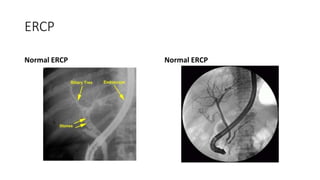

Endoscopic Retrograde

Cholangiopancreatography(ERCP)

• It is combined Endoscopic & Radiological Approach.

• IND:: When USG s/o dilated IHBR with dilated CBD i.e Obstruction is

suspected to be at the lower biliary tract or near

pancreatic head.

ERCP

Normal ERCP Normal ERCP

Biliary stricture due to

cholangiocarcinoma

Bile duct obstruction

from chronic pancreatitis

• Advantages::

• Endoscopic Visualization of

duodenum to rule out duodenal

obstruction.

• Endoscopic Sphincterotomy with

dormia basket removal of CBD

Stone.

• Biopsy & Cytology.

• Endoscopic Biliary Stent placement

for non surgical palliation.

• It is contraindicated in Recurrant

Acute Pancreatitis & Unfavourable

anatomy.

• Complication

1. Pancreatitis

2. Cholangitis

3. Hemorrhage

4. Sepsis